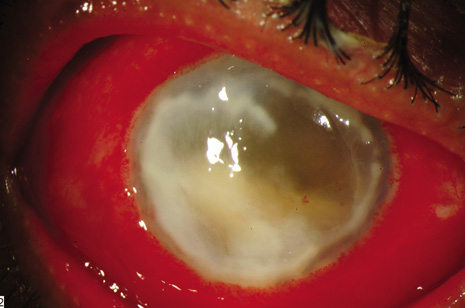

CONJUNCTIVAL FILTERING BLEB-ASSOCIATED ENDOPHTHALMITIS

This category of endophthalmitis is similar to acute postoperative endophthalmitis in that these patients manifest a sudden onset of pain, visual loss, conjunctival congestion, purulent bleb involvement, and the typical diagnostic features of acute-onset endophthalmitis (Fig. 8).10,11,104 Risk factors for this category of endophthalmitis include a history of conjunctivitis, contaminated topical glaucoma medications, the use of contact lenses, and inferior filtering bleb.10,104 The incidence of bleb-related endophthalmitis after a glaucoma-filtration procedure with mitomycin C may be higher than for trabeculectomy without antifibrotic agents.104 The organisms frequently involved in this type of endophthalmitis include streptococcal species8,71 and Hemophilus influenzae. Because of the frequency of these virulent organisms and the generally poor visual acuity outcomes, PPV and intraocular antibiotics are often considered as the initial approach for conjunctival filtering bleb-associated endophthalmitis.

Fig. 8. Delayed-onset endophthalmitis associated with glaucoma filtering blebs. Organisms invade the bleb initially and spread to involve intraocular fluids and tissues. This patient shows characteristic purulence of the filtering bleb, conjunctival congestion, hypopyon and fibrin in the pupil. Streptococcus pneumoniae was isolated from the vitreous specimen.

It is important to distinguish between a localized bleb infection (blebitis) and true endophthalmitis associated with an infected filtering bleb.11 The former category can be treated with intensive topical, subconjunctival, and possibly systemic antibiotics while the latter category can be treated in a manner similar to acute-onset postoperative endophthalmitis (Fig. 9).

Fig. 9. Bleb-associated endophthalmitis occurring two years following glaucoma filtering surgery. Left: Marked purulence of the bleb, hypopyon, and fibrin in the pupil. Visual acuity was reduced to hand motion. The patient was treated with a vitreous tap and injected with intravitreal antibiotics. Right: Coagulase-negative staphylococcus was isolated from the vitreous. Final visual acuity was 20/400 because advanced glaucomatous disease limited visual recovery.